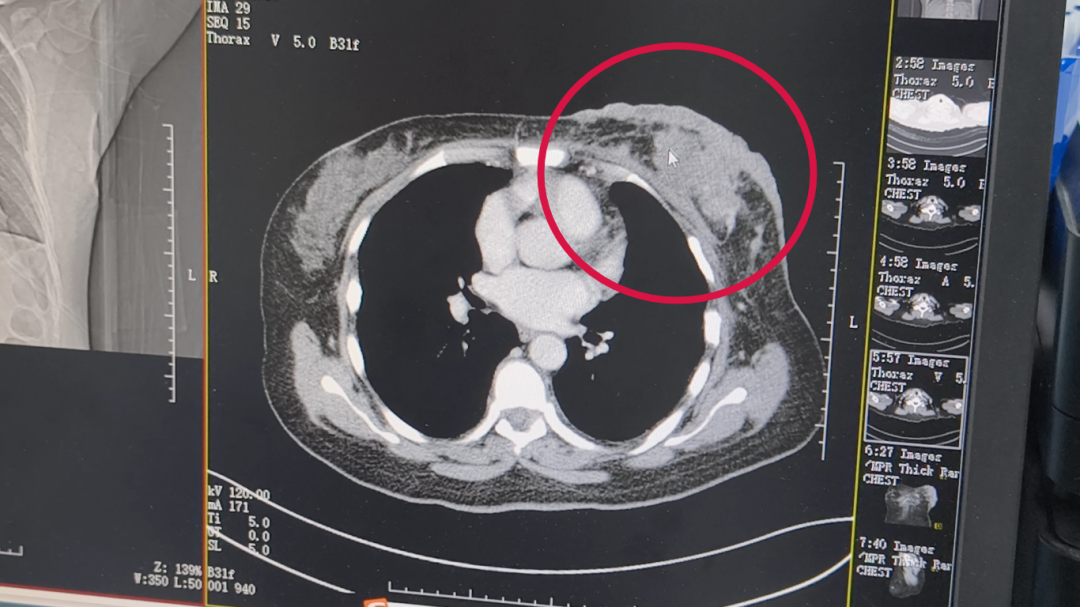

入院时,阿平乳腺上出现很多结节,考虑到肿瘤具有异质性和异型性,重新活检提示为三阴性乳腺癌。为此,阿平接受介入治疗。除了第一次副反应有点大,后面的情况越来越好。其中最直观的就是乳房的皮肤从硬邦邦、疙疙瘩瘩逐渐变淡、结痂;影像资料也提示肿瘤较前缩小。

第一次(2024年11月)入院时影像结果

2025年4月14日 影像结果

“我们曾做好了最坏打算,但现实却不断反转,当然,我们喜欢这种反转!”如今阿平与家人一同来复大诊疗,就如同度假一般,她们非常感谢复大医护人员的专业与贴心,在治疗过程中,医护不仅关注疗效,还重视她的心理状态。同时,因人而异,因症施策,及时调整治疗方案也让她非常满意。目前,阿平的疗效评估“PR”(部分缓解),后续仍以化疗为主维持治疗。